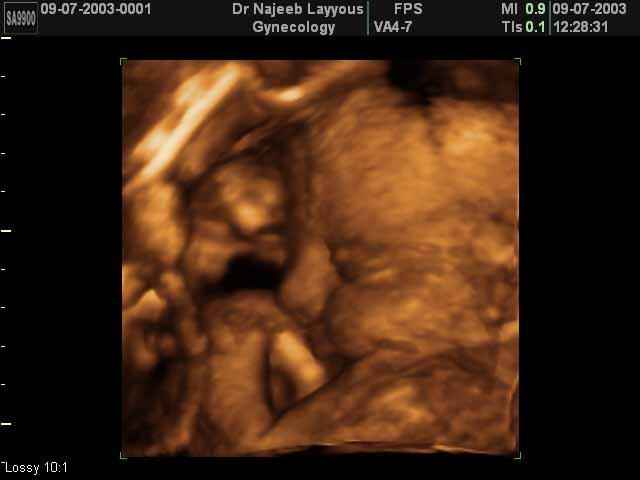

- 3D Fetal Profile Ultrasound Scan Photos

3D Fetal Profile Ultrasound Scan Photos | Dr N Layyous